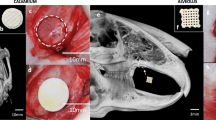

3D µCT image reconstruction gave an overview of the optical defect sizes of the different experimental groups at week 0, 4 and 8 post-surgery, as a result of the surgical procedure (Fig. 5A–E). µCT analysis at week 4 demonstrated an enhanced relative bone volume (BVweek 4 − BVweek 0) in the iNCC-MPC-BMP6 group in the frontal bone compared to defect only and Ink-Bone only. At 8 weeks, the relative BV was increased in the iNCC-MPC-BMP6 as well as in the iMSC-BMP6 groups compared to defect only. No significant differences in bone volume were detected between any of the other groups in the frontal bone. Except in the BM-MSC BMP-6 group, in all frontal bone groups treated with Ink-Bone, the relative bone volume was increased compared to parietal bone (Fig. 5F).

Cranial defect filling with Ink-Bone seeded with iNCC-MPC-BMP6 results in increased bone volume in the frontal bone. (A) Surgical approach to create calvarial defects in the frontal and parietal bone. Shown is the fixated cranium with circular defects in the frontal and parietal bone. (B) Filling of the defects with Ink-Bone. (C) Crosslinking of Ink-Bone using CaCl2 solution. (D) The sutured skin. (E) 3D reconstruction of the cranial defects treated with Ink-Bone with and without cells or untreated at weeks 0 and 4. (F) Violin plots showing the change in bone volume in the different experimental groups and implantation sites between weeks 0 and 4, and 0 and 8. *p < 0.05, **p < 0.01, ***p < 0.001, ****p < 0.0001, n ≥ 5.